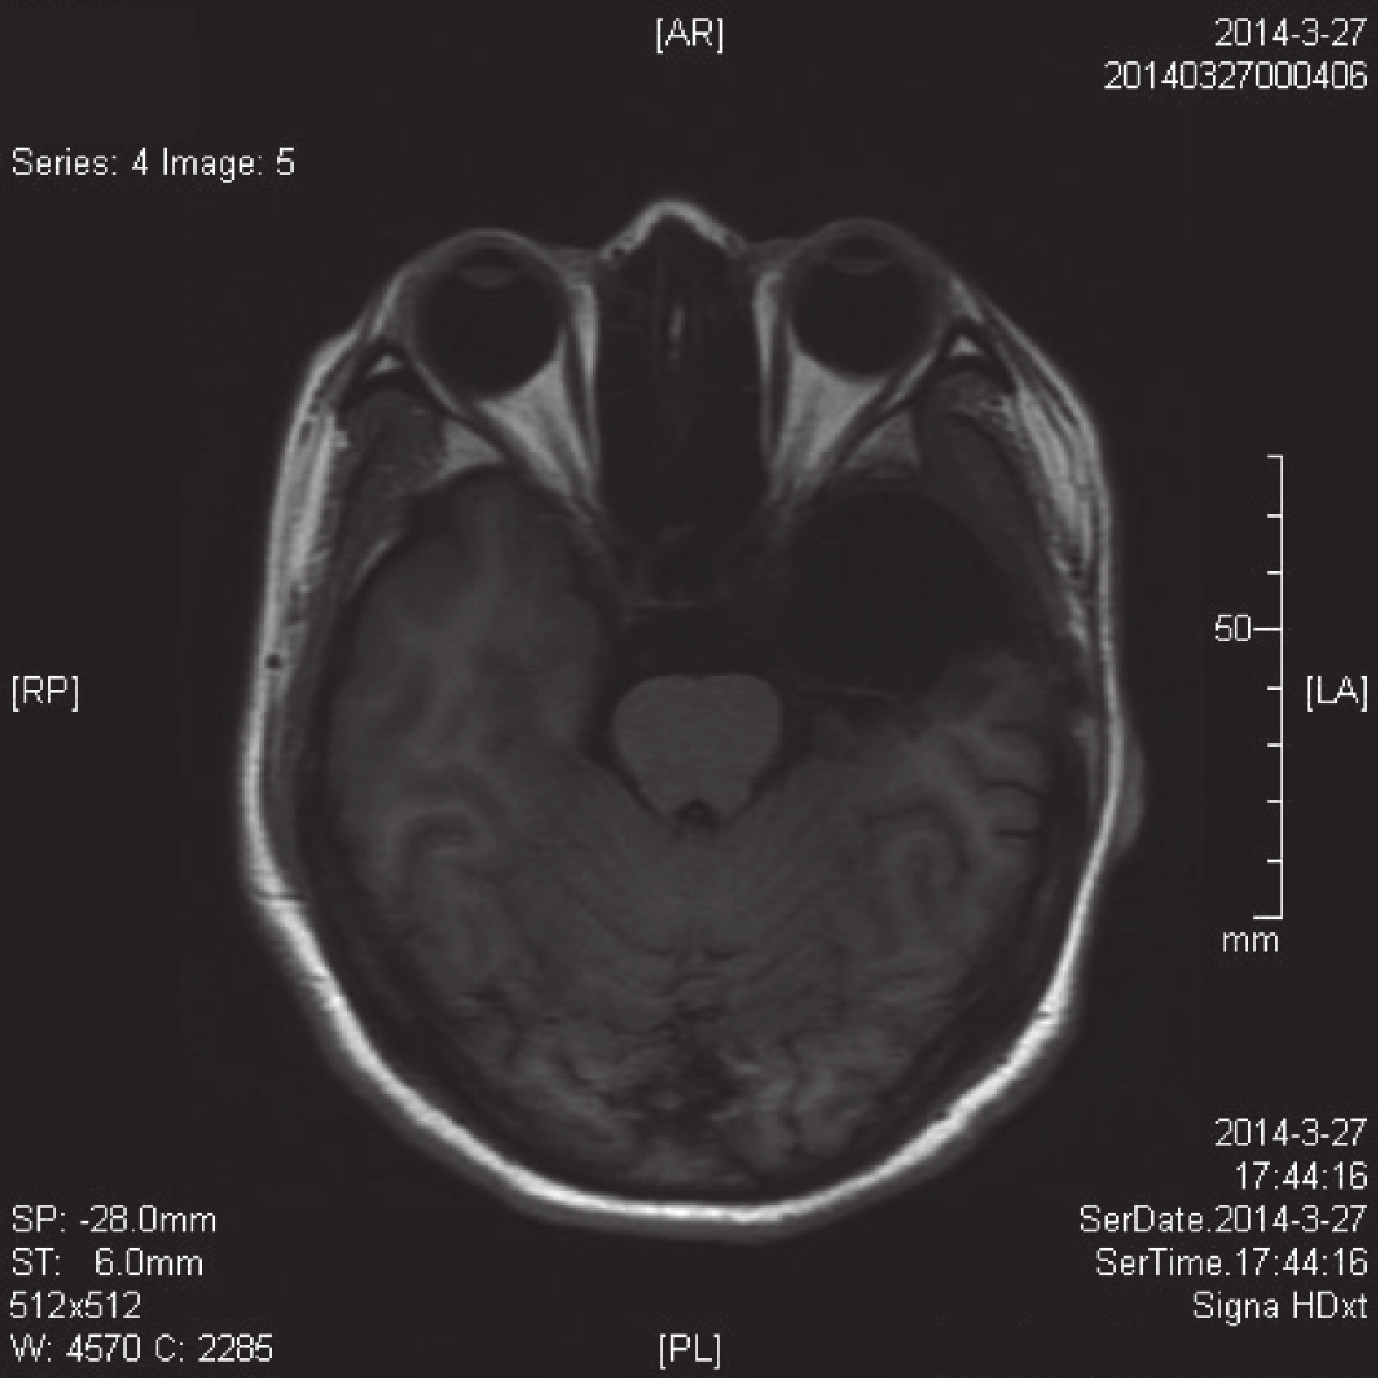

所有患者術后 6~8 h 均復查 CT,術后 1 年復查 MRI(圖 9、10),均提示前顳葉切除術后改變。所有患者術后兩周行常規 EEG 復查,均見手術側有慢波改變。術后病理檢查發現,顳葉皮層、海馬和杏仁核神經元顯著減少、廣泛萎縮、嗜酸性改變,膠質細胞彌漫增生,有衛星現象。